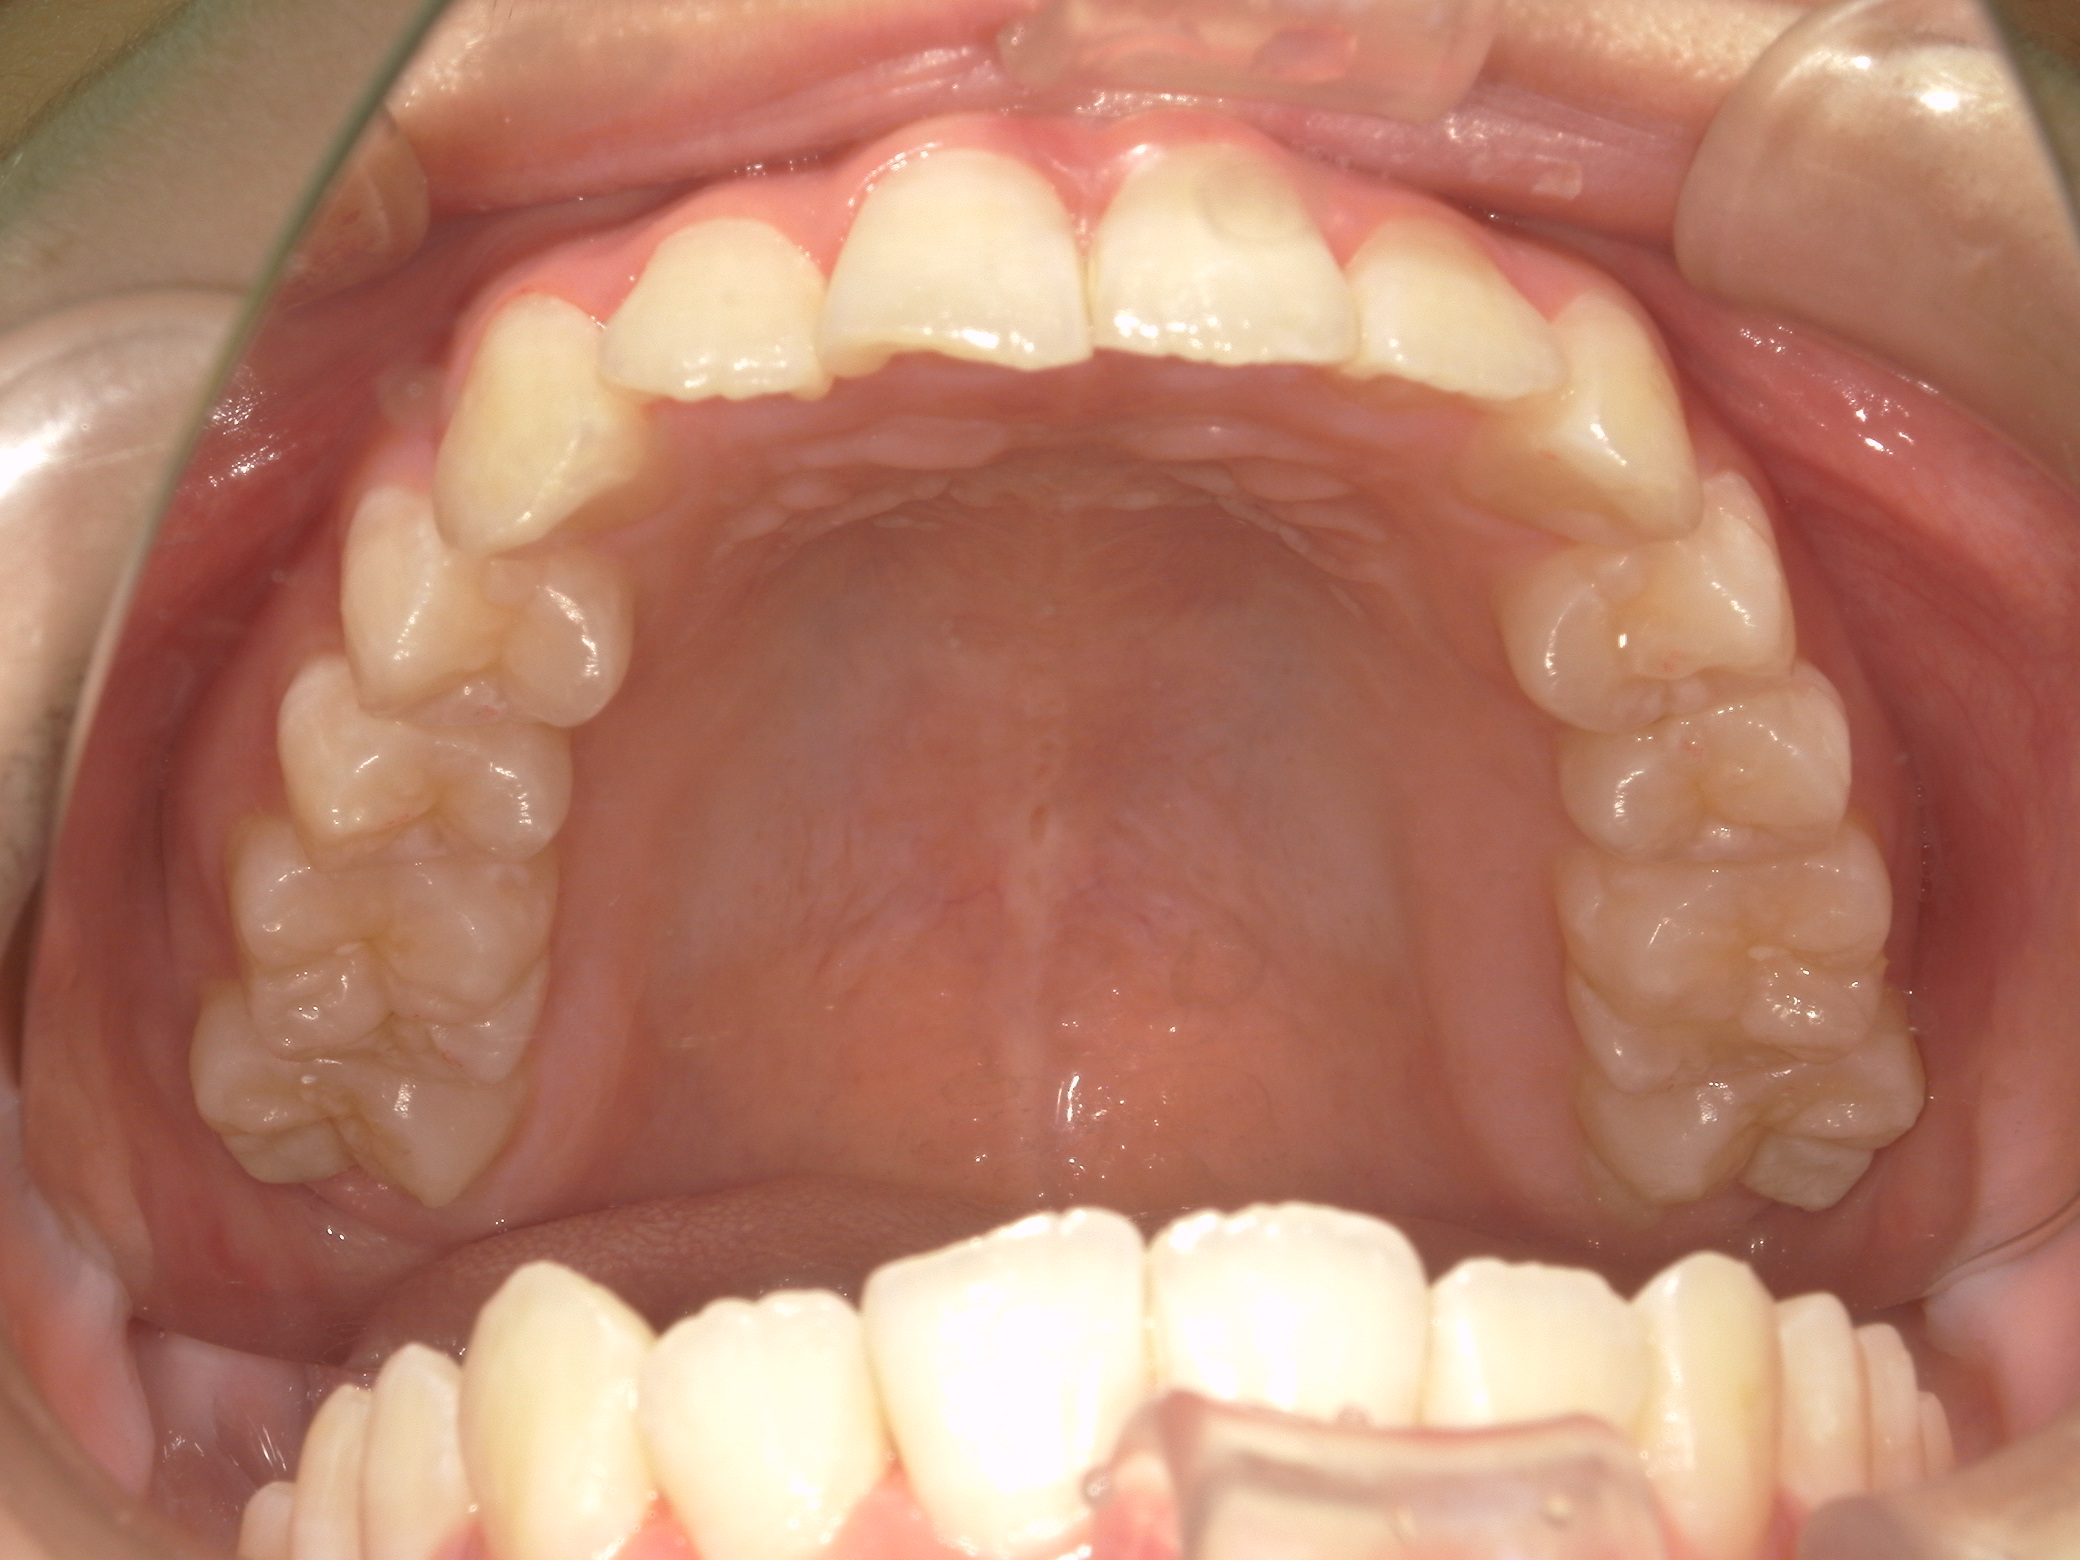

【中学生】インビザラインフル 上顎前突(出っ歯)と 叢生(でこぼこ) を改善

小学生で開始

インビザライン フル

でこぼこ

出っ歯

過蓋咬合

非抜歯

2期治療のみ

Before

After

治療期間

2年

治療開始

14歳

種類

インビザライン矯正

使用装置

インビザラインフル

コメント

先天欠損歯がある患者さんです。

途中 留学されたので 治療を進める速さを遅くした時期もありました。

しっかりはめてくれて 奥歯の咬み合わせも改善し治っています。